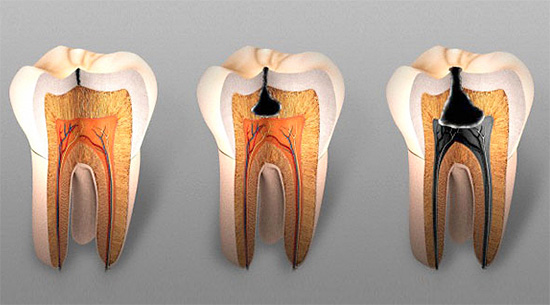

Poiché la carie profonda è l'ultimo stadio della distruzione cariata, ha solo una caratteristica clinica (lo stesso vale per i metodi diagnostici e terapeutici). Nella vita reale, può essere abbastanza difficile determinare lo stadio di distruzione dei tessuti dei denti duri: la carie media e profonda spesso hanno poche differenze.

Se vuoi assicurarti che il dolore al dente sia associato a carie profonde e non a qualcos'altro, puoi provare a condurre una diagnosi differenziale indipendente. Prima di tutto, devi assicurarti che questa non sia polmonite: con la carie, il nervo dentale è ancora intatto e con la polipite, i batteri si sono già fatti strada nella camera pulpare e stanno lentamente distruggendo i tessuti molli qui. Di conseguenza, nel primo caso, il trattamento minaccerà solo con l'installazione di un sigillo e nel secondo, sarà necessario rimuovere il "nervo", pulire i canali, riempirli, ecc., Cioè la procedura sarà molto più complicata (e costosa).

- Nella pulpite acuta, i dolori sono acuti e spontanei (specialmente di notte), cioè sorgono da soli, in contrasto con la carie profonda, in cui il dolore si verifica solo da sostanze irritanti esterne.

- Con la carie profonda, il dolore delle sostanze irritanti passa rapidamente e, con la polpite, il dente fa male per molto tempo.

- a pulite cronica la cavità cariata può comunicare con la camera pulpare, quindi, quando il cibo viene ingerito, si verificano spesso forti dolori che non durano a lungo.

Generalmente, con carie profonde, il suono è doloroso in tutto il fondo. La camera pulpare (il punto in cui si trova il "nervo" del dente) non è aperta. Nella forma acuta di pulpite, il suono è spesso doloroso in un solo punto e, nelle forme croniche, la polpa può persino essere aperta e il "nervo" durante il suono può sanguinare dolorosamente.

I raggi X passano facilmente ammorbiditi con il tessuto della carie e nell'immagine viene visualizzata una macchia scura di una certa area in proporzione alla dimensione della cavità. Il messaggio di un tale "punto" in un quadro con una camera pulpare indica quasi sempre un'infiammazione del "nervo" e lo sviluppo di una complicazione della carie profonda: la pulpite.